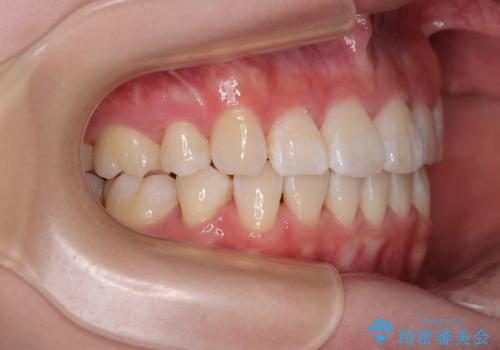

- 前歯がくちばしのように飛び出していることを気にして来院された患者様です。

唇が前方に突出している横顔が気になっているため、上下左右の第一小臼歯4本を抜歯し、ワイヤー装置にて矯正治療を行うこととしました。

わずか2年弱で一気に口元が変化し、患者様には大変満足していただけました。